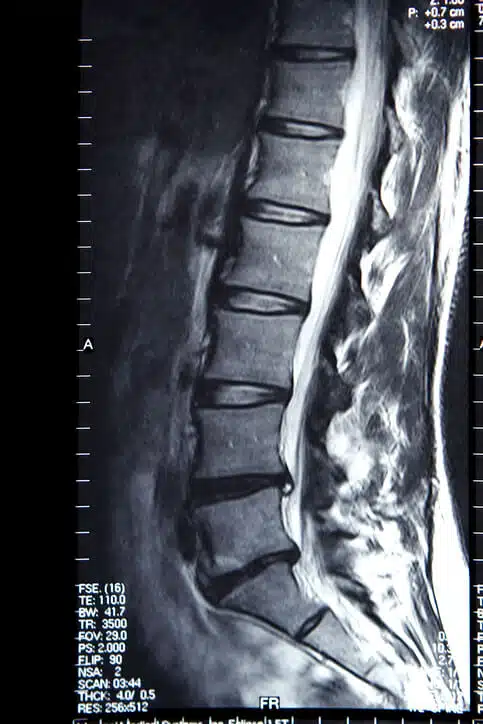

MRI scan of the lumbar spine

Follow-up evaluations confirmed improved spinal stability and nerve decompression through conservative management.